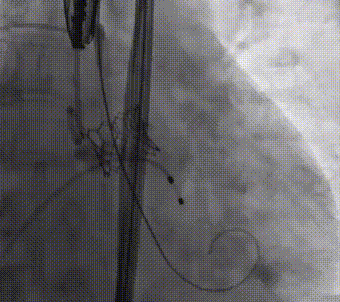

释放后造影及超声评估瓣膜活动良好,轻度瓣周漏;

瓣膜释放后造影评估

与GISE主席团专家在线沟通后,以原球囊再次扩张瓣膜1次;

瓣膜后扩

经食道超声提示瓣膜位置、形态及功能满意,未见明显反流,瓣周漏较前好转,微量瓣周漏,复查造影瓣周漏明显减少至微量,左右冠脉无阻塞,人工瓣膜植入深度约:无冠窦侧为1mm,左冠窦侧为3mm。复查左心室及升主动脉收缩舒张压分别为157/9mmHg、154/71mmHg。手术取得圆满成功。

术后食道超声评估

术后复查造影